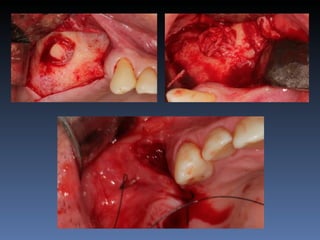

José Luis Bergamim

Idade – 53 anos

Sexo – Masculino

Raça – Caucasiana

ASA – II

Data- 25-04-2012

Diagnóstico:Desdentado parcial maxila

zona 2.2, defeito horizontal

Plano de tratamento: Reabilitação com 1 bloco “onlay”

autógeno proveniente do Ramo de Mandíbula; para

reabilitação futura com implante endo-ósseo.

Espessura Residual

2,5 mm

Defeito Horizontal

Espessura após reabilitação

8,8 mm

Preenchimento de “Gaps”

com particulado ósseo

e

Sutura

Descorticalização   Fixação do bloco “onlay”